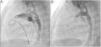

A coil was used in 139 patients (62.9%) and an Amplatzer duct occluder was used in 79 patients (35.7%). In the three remaining patients (1.4%), an Amplatzer vascular plug was used for closure (Figures 2-8). Despite the higher overall rate of coil device implantation, Amplatzer duct occluder usage had been clearly superior since 2011. Of all coil devices used, 55% were either 4x4 mm or 5x4 mm in size (Figure 9), and of all duct occluder devices used, 72% were Amplatzer duct occluder I 6x4 mm or 8x6 mm in size (Figure 10), which correlates to the fact that most patients who were referred had small- to moderate-sized ductus arteriosus. While ADO II and ADO II AS devices can be implanted in a retrograde fashion, only on two occasions was a retrograde deployment performed (both ADO II devices).

Both patients with history of previous PDA closure were successfully treated. The first was a seven year-old child who had a coil implanted at age three. The procedure was technically difficult, requiring a guidewire capture using a snare catheter to go through the residual PDA (Figure 11), and an Amplatzer duct occluder II 3x4 mm device was implanted successfully. The second patient was a 19 month-old child with PDA and pulmonary hypertension after an unsuccessful surgical ligation. In this case, sizing with a Tyshak balloon was required before implanting an Amplatzer duct occluder II 3x4 mm device (Figure 12).